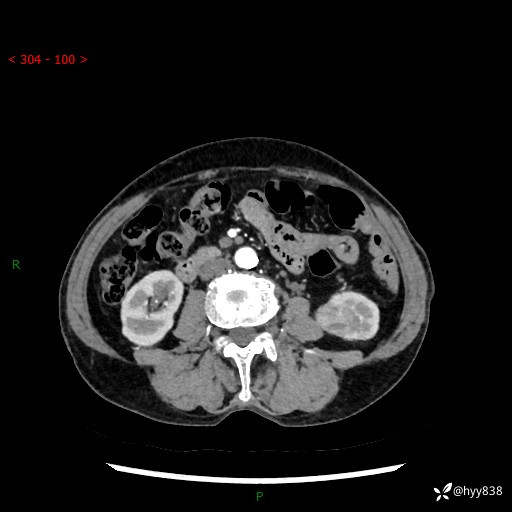

72岁/女,检查发现左肾占位1天。为了满足诊断,常规四期后,又加了延迟期-结果公布~

【患者信息】:72岁/女

【主诉】:检查发现左肾占位1天

【现病史及既往史】:患者于1天前检查发现左肾占位,无畏寒发热,无咳嗽咳痰,无腰腹部疼痛不适,无肉眼血尿、无尿频尿急症状,起病来,患者未行特殊治疗,为求进一步诊治,门诊以"左肾占位"收治入院。 发病来患者精神、饮食、睡眠良好,小便如上,大便正常,体重无明显变化。

【检查】:肾脏CT平扫+增强